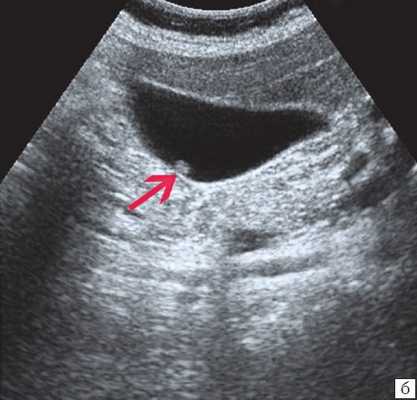

При поступлении в НМИЦ хирургии им. А.В. Вишневского пациентке выполнена фистулохолангиография (рис. 1), - это исследование показало, что тотчас после слияния долевых протоков печени отмечается полный блок общего печеночного протока. По классификации Strasberg с соавт., данную стриктуру можно отнести к типу Е2; по классификации Э.И. Гальперина - к типу «0».

Учитывая данные анамнеза и результаты обследований, по принятой в хирургическом эндоскопическом отделении тактике первым этапом была выполнена эндоскопическая ретроградная холангиография и оценка проходимости общего желчного протока, достоверно определена протяженность стриктуры и интраоперационно решен вопрос о возможности эндоскопического лечения.

В данном случае у пациентки обнаружена рубцовая стриктура (сужение) общего желчного протока, при которой его диаметр уменьшился до 1 мм на значительном протяжении.

Специальную сверхтонкую струну-проводник удалось провести в сегментарный проток правой доли печени (рис. 2), после чего принято решение первоочередно расширить просвет протока специальными эндоскопическими бужами (рис. 3, 4), постепенно увеличивая диаметр последних.